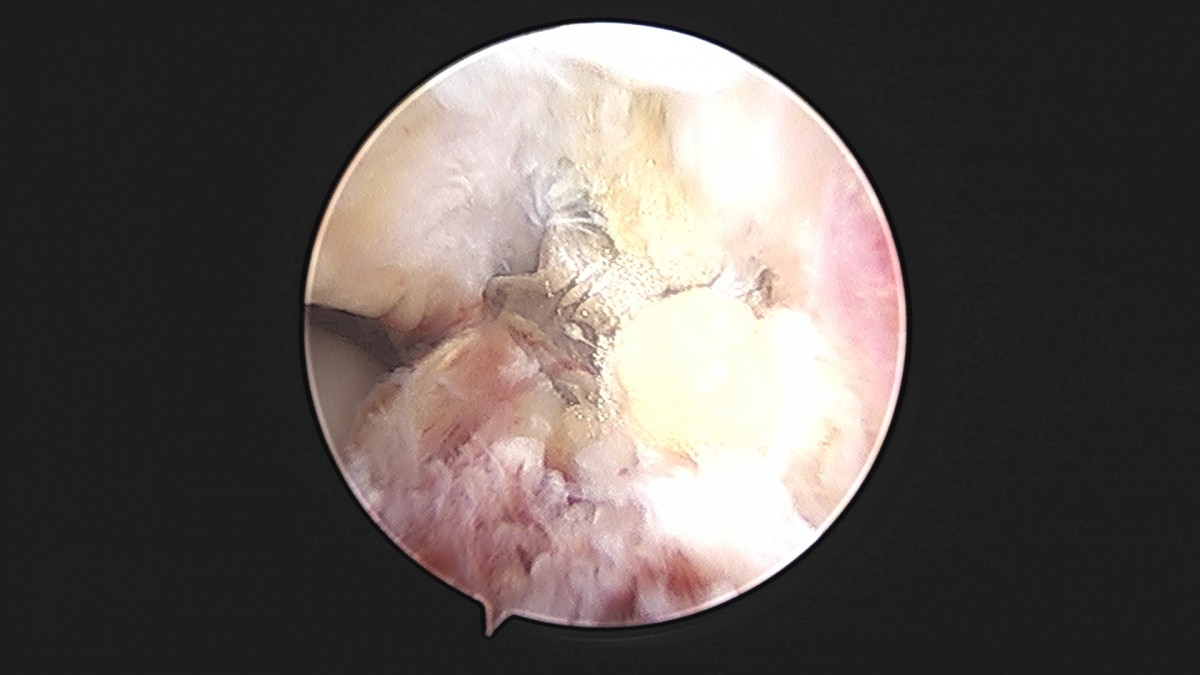

이재상원장님 발목 인대 봉합술 박찬O 환자

dae765e4d9ac96aee867c9d6292d8784_1758007286_1952.jpg